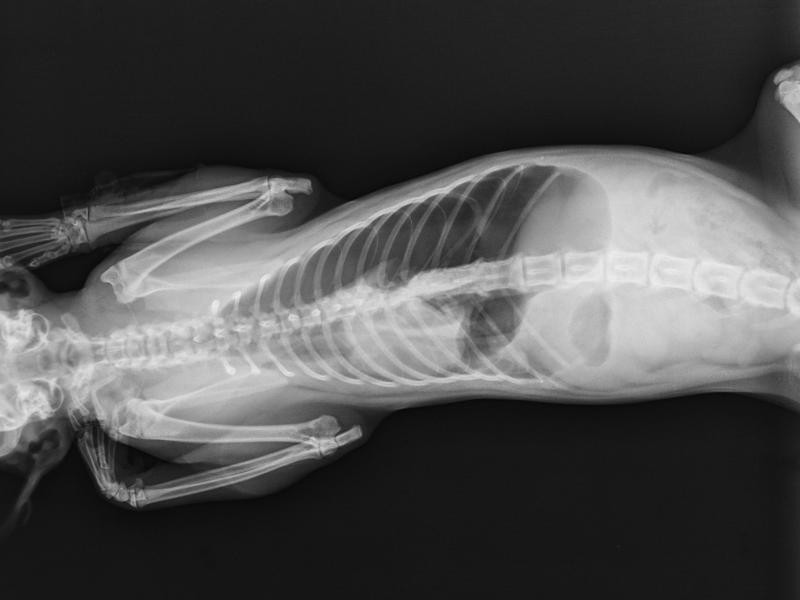

Em muitos casos, o diagnóstico é confirmado por meio de radiografias torácicas e ultrassonografia, que mostram o deslocamento dos órgãos abdominais. O tratamento cirúrgico deve ser feito o quanto antes para evitar complicações respiratórias graves e risco de morte.

A Correção de Hérnia Diafragmática Veterinária é uma cirurgia que visa reconstruir o diafragma e reposicionar corretamente os órgãos abdominais que migraram para o tórax. Durante o procedimento, o veterinário repara a abertura no músculo diafragmático e devolve órgãos como fígado, estômago e intestinos à cavidade abdominal, restabelecendo a anatomia e a função respiratória do animal.